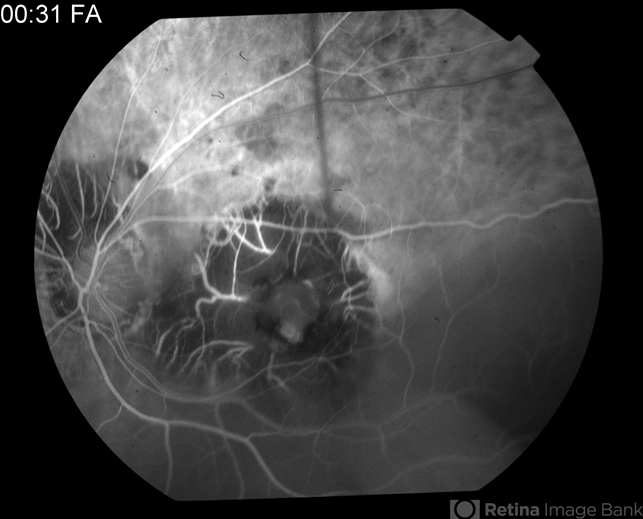

- tuberculosis, macular scar

- 0:31 second FA of 81-year-old male - old tuberculosis scar.